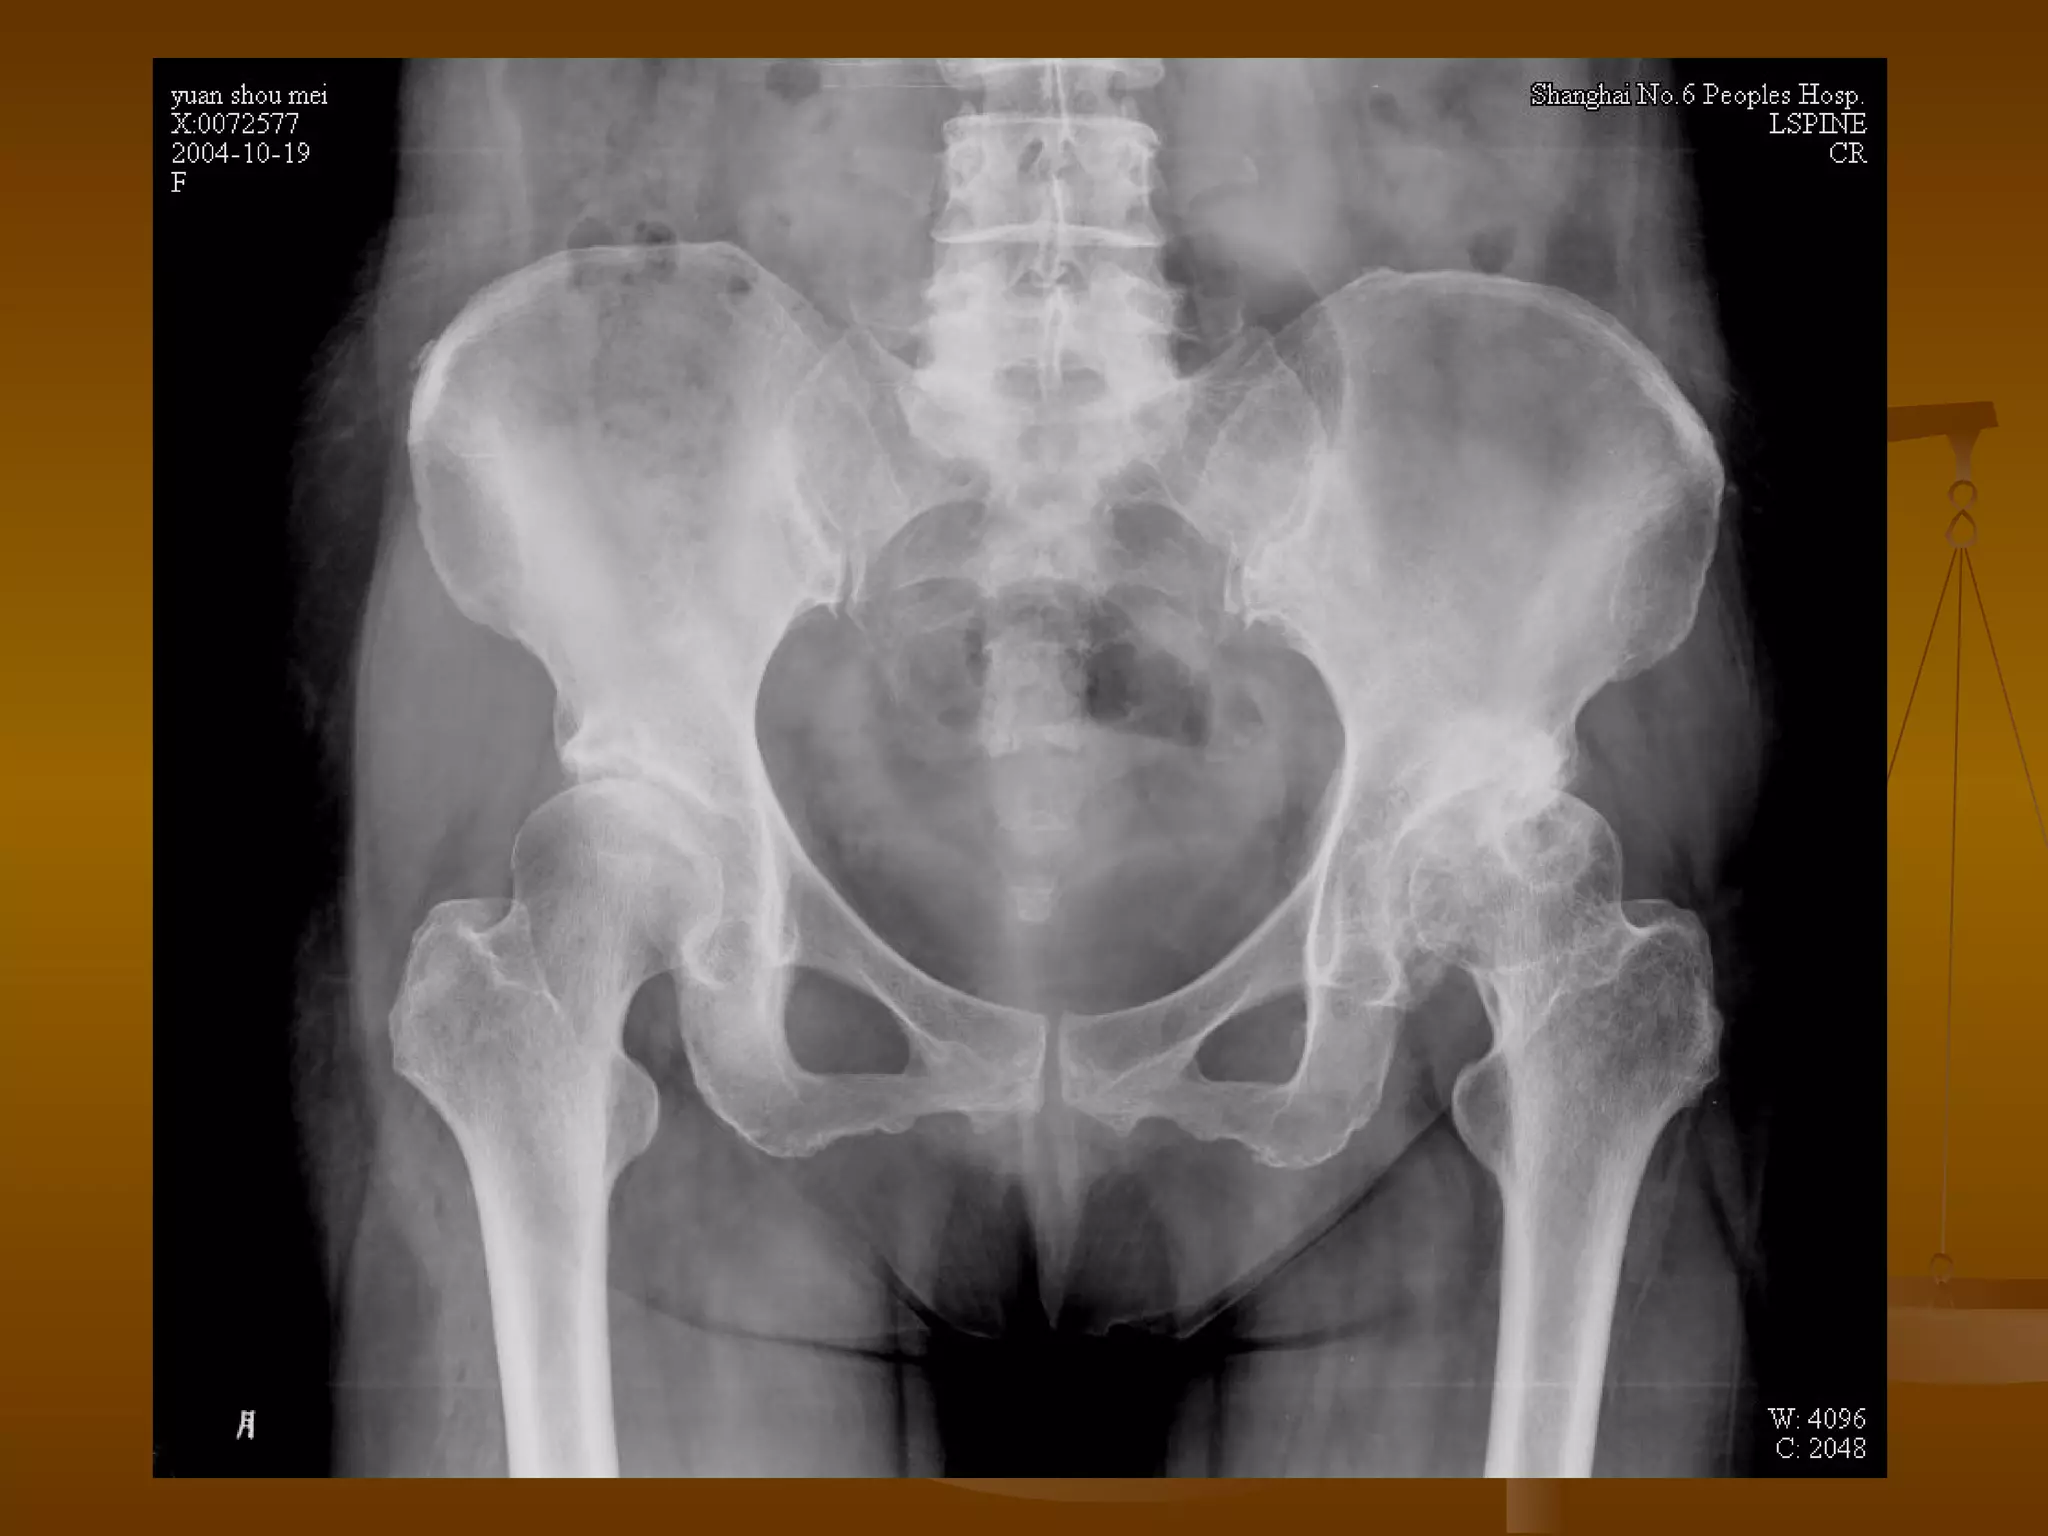

股骨头缺血坏死的鉴别诊断 扁平髋 幼年时曾患 Legg-calve-perthes 病,成年后可遗留股骨头变形,并继发退变。 但骨小梁清楚,密度均匀,股骨头塌陷、分节碎裂不明显。

股骨头缺血坏死的鉴别诊断 退行性骨关节炎 先出现关节软骨变薄、中断,关节间隙狭窄。 股骨头关节面下囊变、股骨头变形、股骨头毁损。 髋臼关节面骨质增生、囊变。